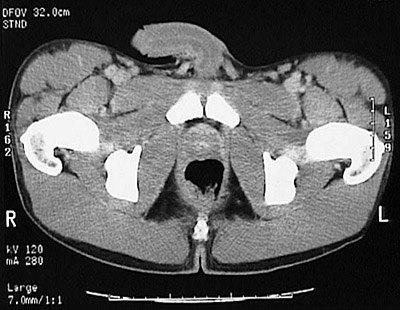

[Pubic Symphysis] This is a normal pelvic CT scan in a male demonstrating the penis and penile urethra and right spermatic cord and left spermatic cord and right ischial tuberosity and left ischial tuberosity and right femoral head and trochanter and left femoral head and trochanter and pubic symphysis and prostate and rectum and right femoral vein and right femoral artery and left femoral vein and left femoral artery and coccyx and gluteal fold and obturator internus muscle and obturator externus muscle and quadratus femoris muscle and pectineus muscle and iliopsoas muscle and rectus femoris muscle and sartorius muscle and tensor fasciae latae muscle and gluteus medius muscle and gluteus maximus in the pelvis.